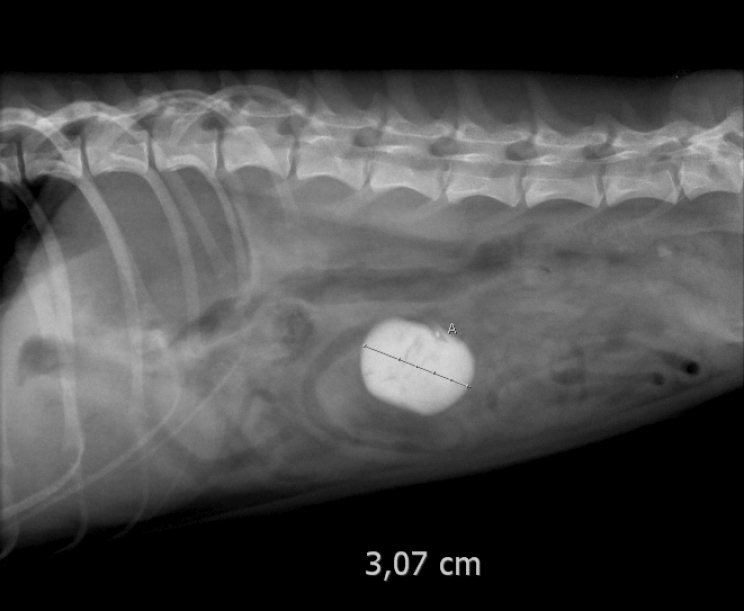

Nel caso di oggetti metallici, sassi o ossa, oggetti densi che si vedono bene nelle radiografie, le cose saranno più semplici perché sappiamo già dove cercare; per le cose meno dense come plastica o spago le cose sono più complesse, perché non sempre si riesce a capire che ci sono (non si vedono nelle lastre); è il padrone a dover seguire il cane quando è a casa e cercare di capire se ci sia un oggetto mancante, in modo da poter dare tutte le possibili informazioni utili al veterinario ed evitando, nel caso la causa non risultasse un corpo estraneo, di aprire inutilmente l'addome dell'animale.